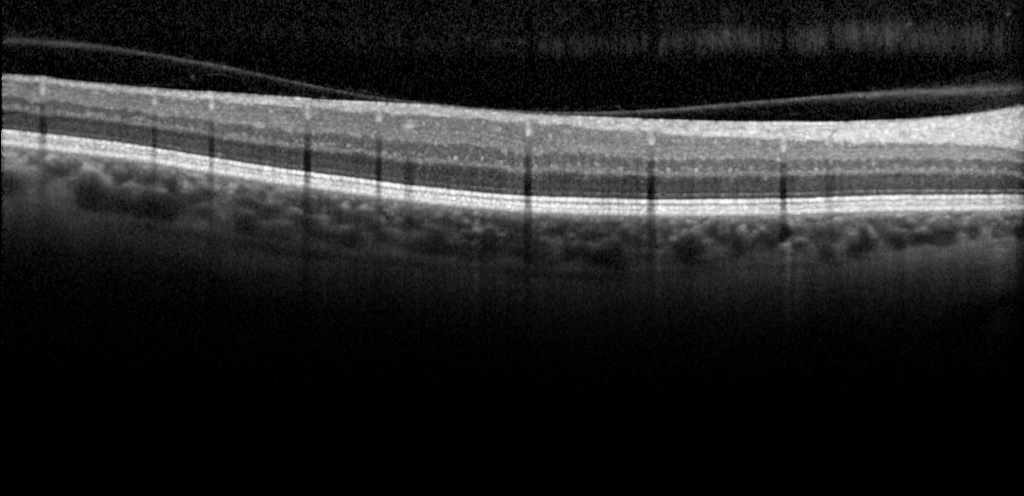

One of Mind+’s recent goals is to develop efficient and accurate Optical Coherence Tomography (OCT) image segmentation and classification algorithms to provide better diagnostic and treatment support for ophthalmologists. We will leverage the most advanced artificial intelligence technology and medical image analysis expertise to continuously optimize our algorithms and improve the accuracy and efficiency of diagnoses.

At the same time, we will work closely with ophthalmology healthcare institutions and experts to understand their needs and feedback, ensuring that our algorithms can meet the practical application scenarios and requirements of our customers. We believe that through our efforts, we can bring more efficient, accurate, and reliable services and support to the ophthalmology healthcare industry.

We are confident that this work will have a significant impact on ophthalmology healthcare, helping doctors diagnose and treat eye diseases more quickly and accurately, and providing patients with better medical experiences and treatment outcomes.